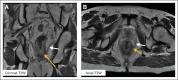

Figures